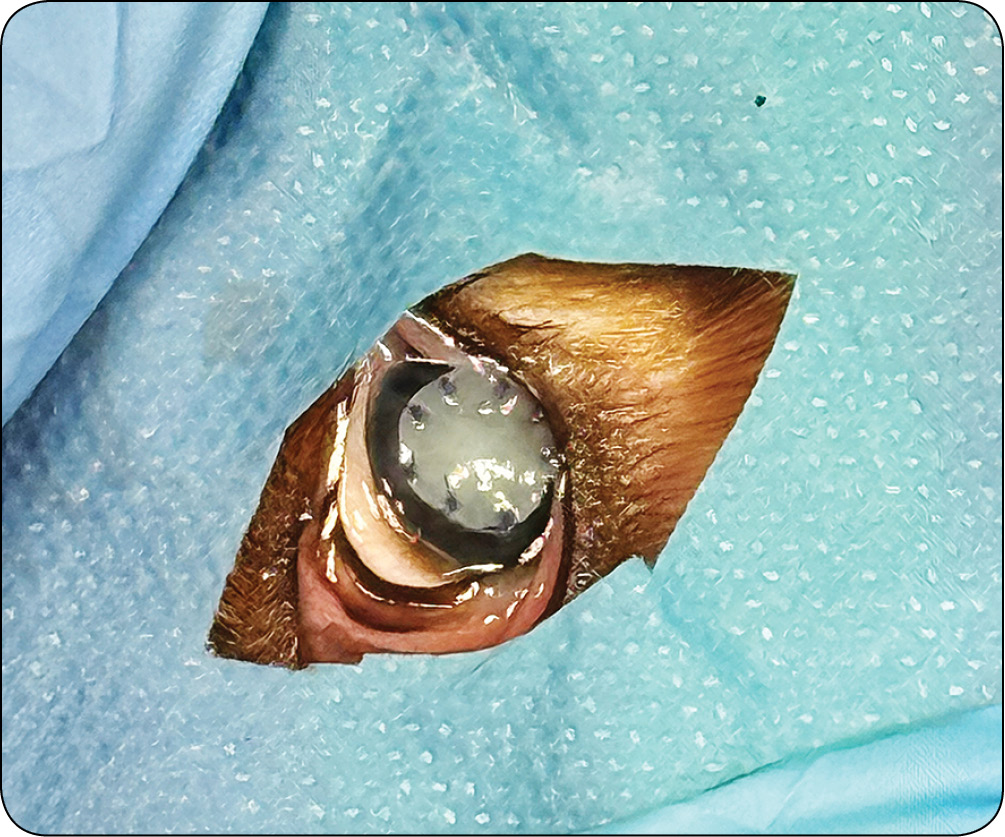

Owrzodzenia rogówki u małych zwierząt – klasyfikacja, diagnostyka i leczenie

Leczenie wspomagające